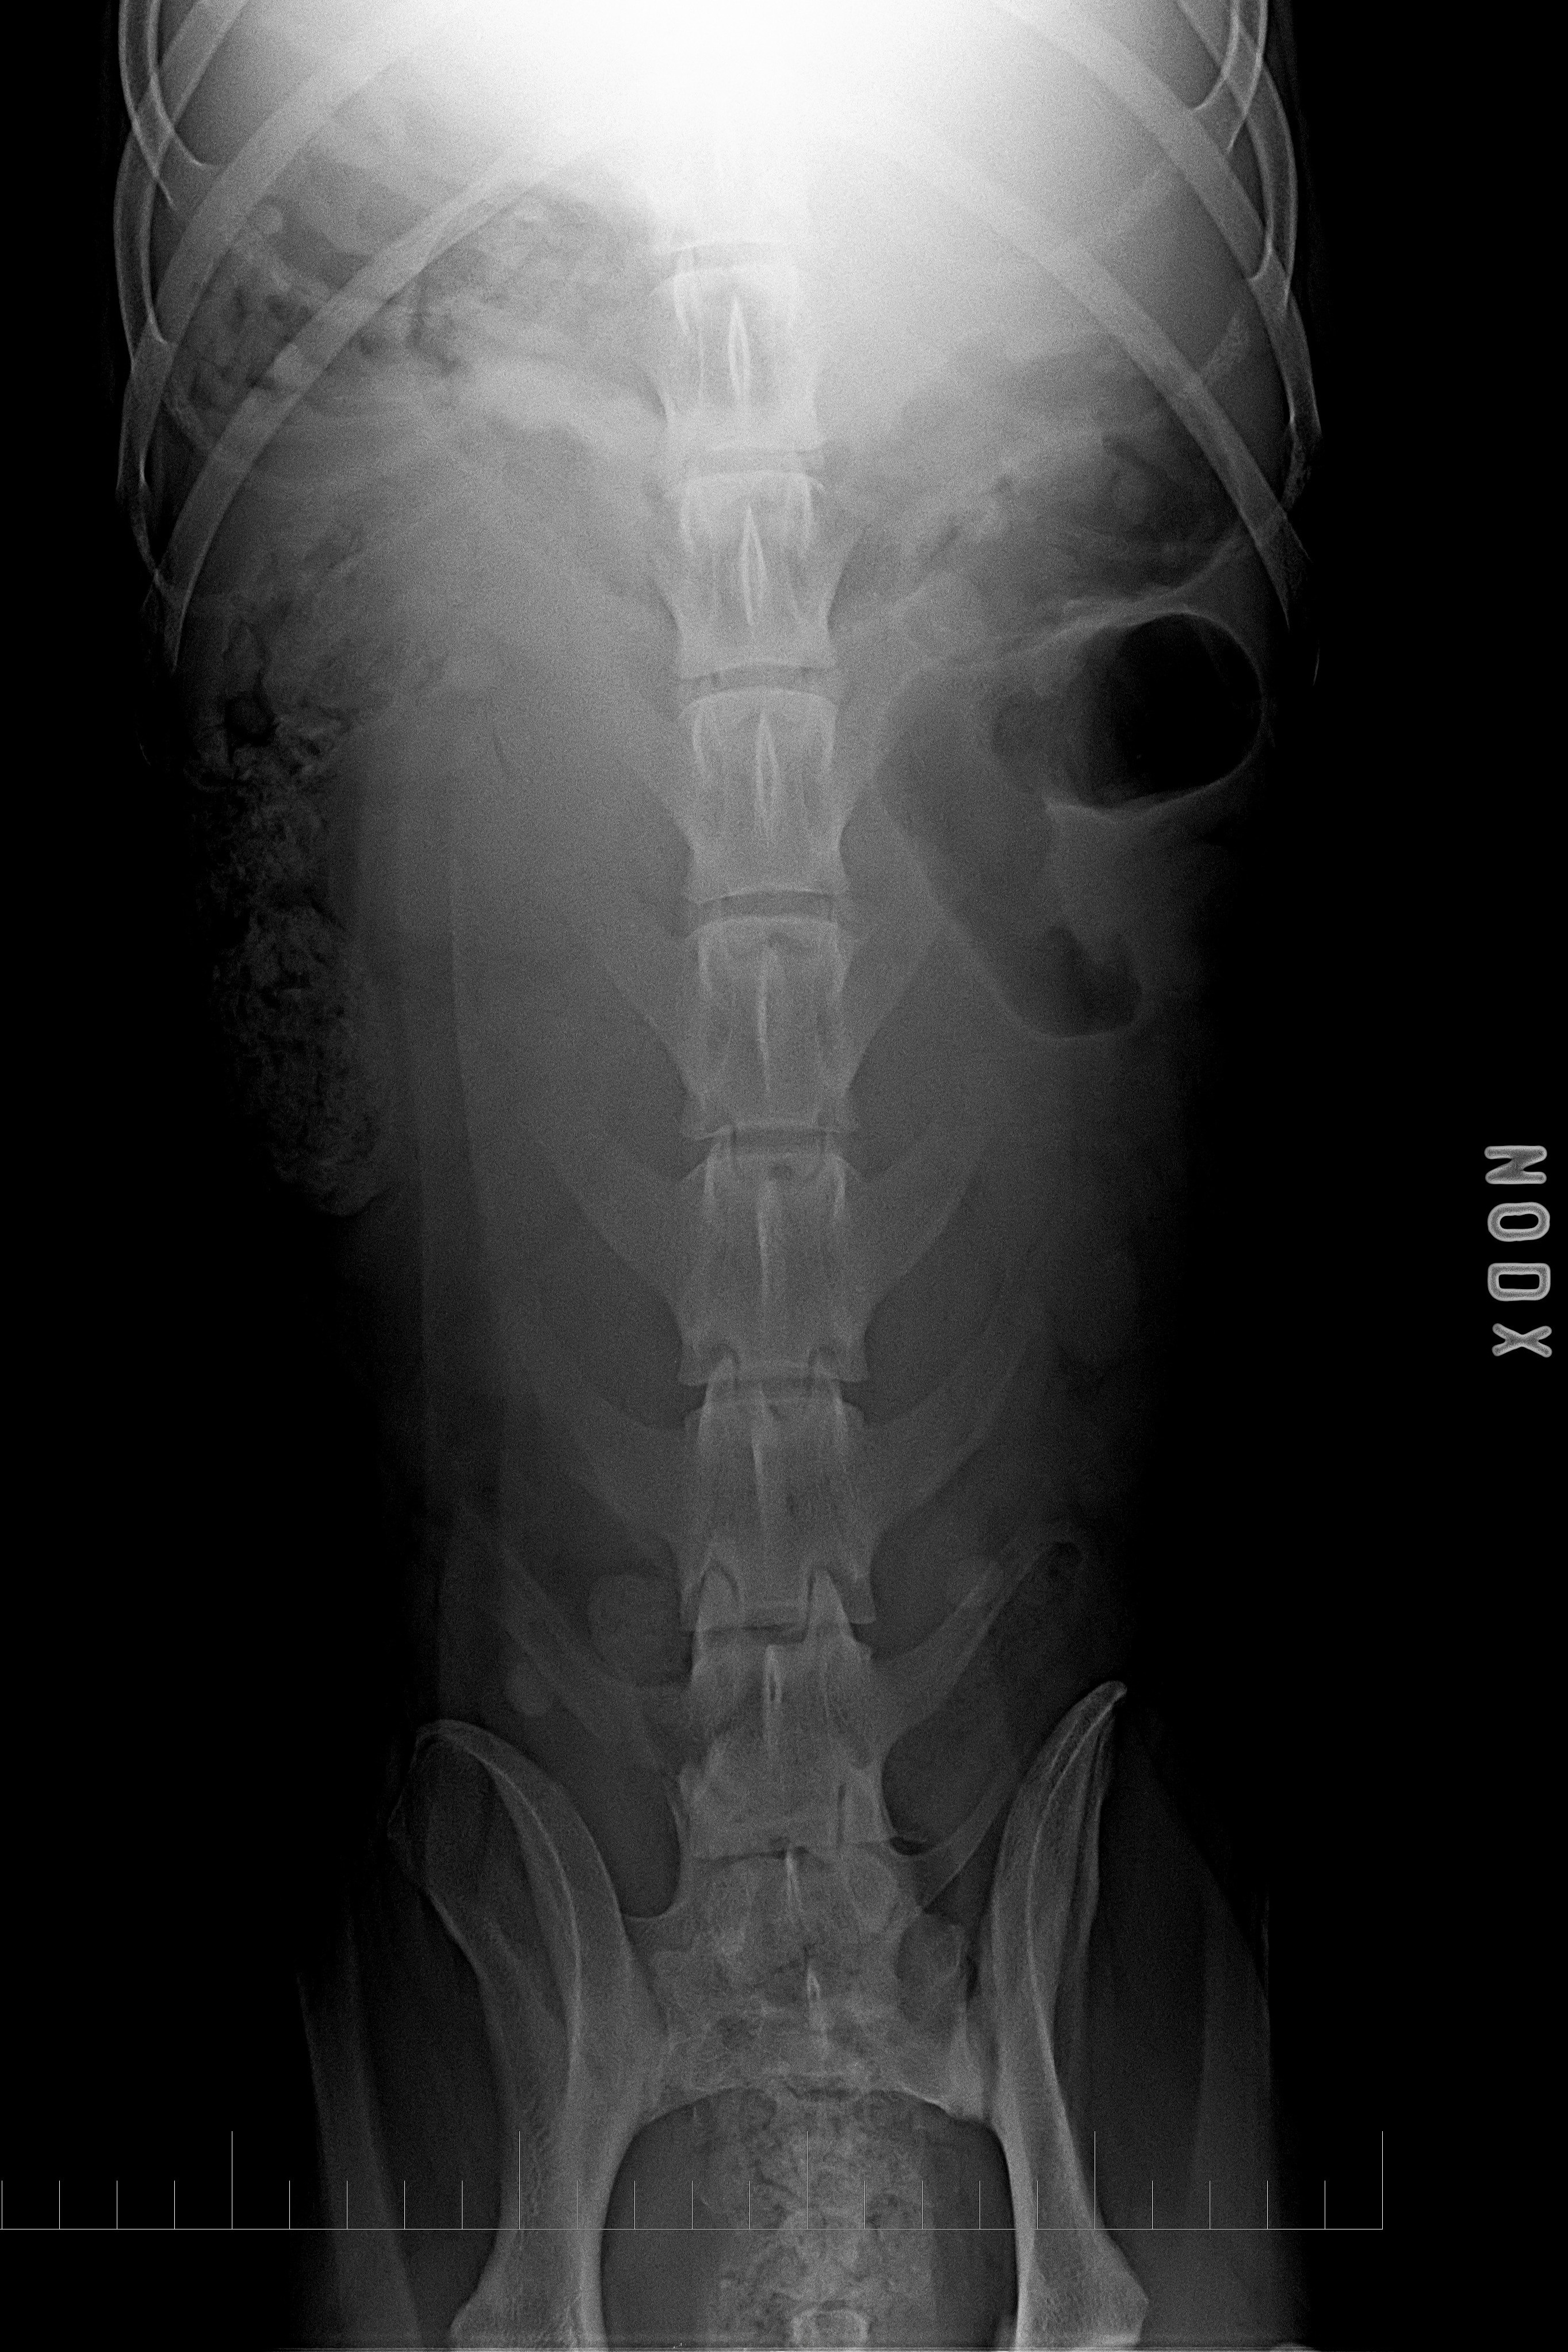

páteř LL

páteř VD

typ 3 u sedmiletého křížence